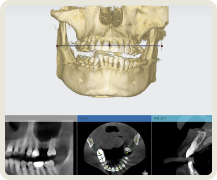

많은 치과의사들이 보철 중심으로 계획된 임플란트 시술의 중요성을 인정합니다.

그리고 이 과정에서 디지털 치과로의 전환이 필요함을 인정합니다.

그러나 비용적인 문제, 새로운 장비 기술 도입의 두려움, 필요성을 못 느끼는 등의 이유로

디지털 진료 방식을 도입하지 못하고 있는 치과가 많습니다.

이제는 임플란트 회사, 임플란트 브랜드 선택의 관점에서 벗어나서 임플란트 수술 진단부터 최종 치아 제작까지. 이 모든 과정에서 보철학적 목표를 디지털 방식으로 어떻게 완성해 내는지가 선택의 관점이 되어야 합니다.

이로운 치과는 간단하고 정확하며 안전한 치료를 위한 디지털 진료 방식을 지향합니다.

이로운치과 치료 과정

이로운치과의 디지털 임플란트 과정

1

implant

CT

2

Oral Scanner

3

3Shape Implant Studio

4

3D Printer

5

15년 노하우의

디지털 가이드 임플란트 수술

6

7

Custom Abutment Design and Milling

8

Zirconia Crown Design and Milling, Sintering

모든 과정은 이로운치과의 의료진과 디지털 치과기공 전문인 와이앤씨 기공소 와의 긴밀한 커뮤니케이션 하에 협업하여 진행합니다.